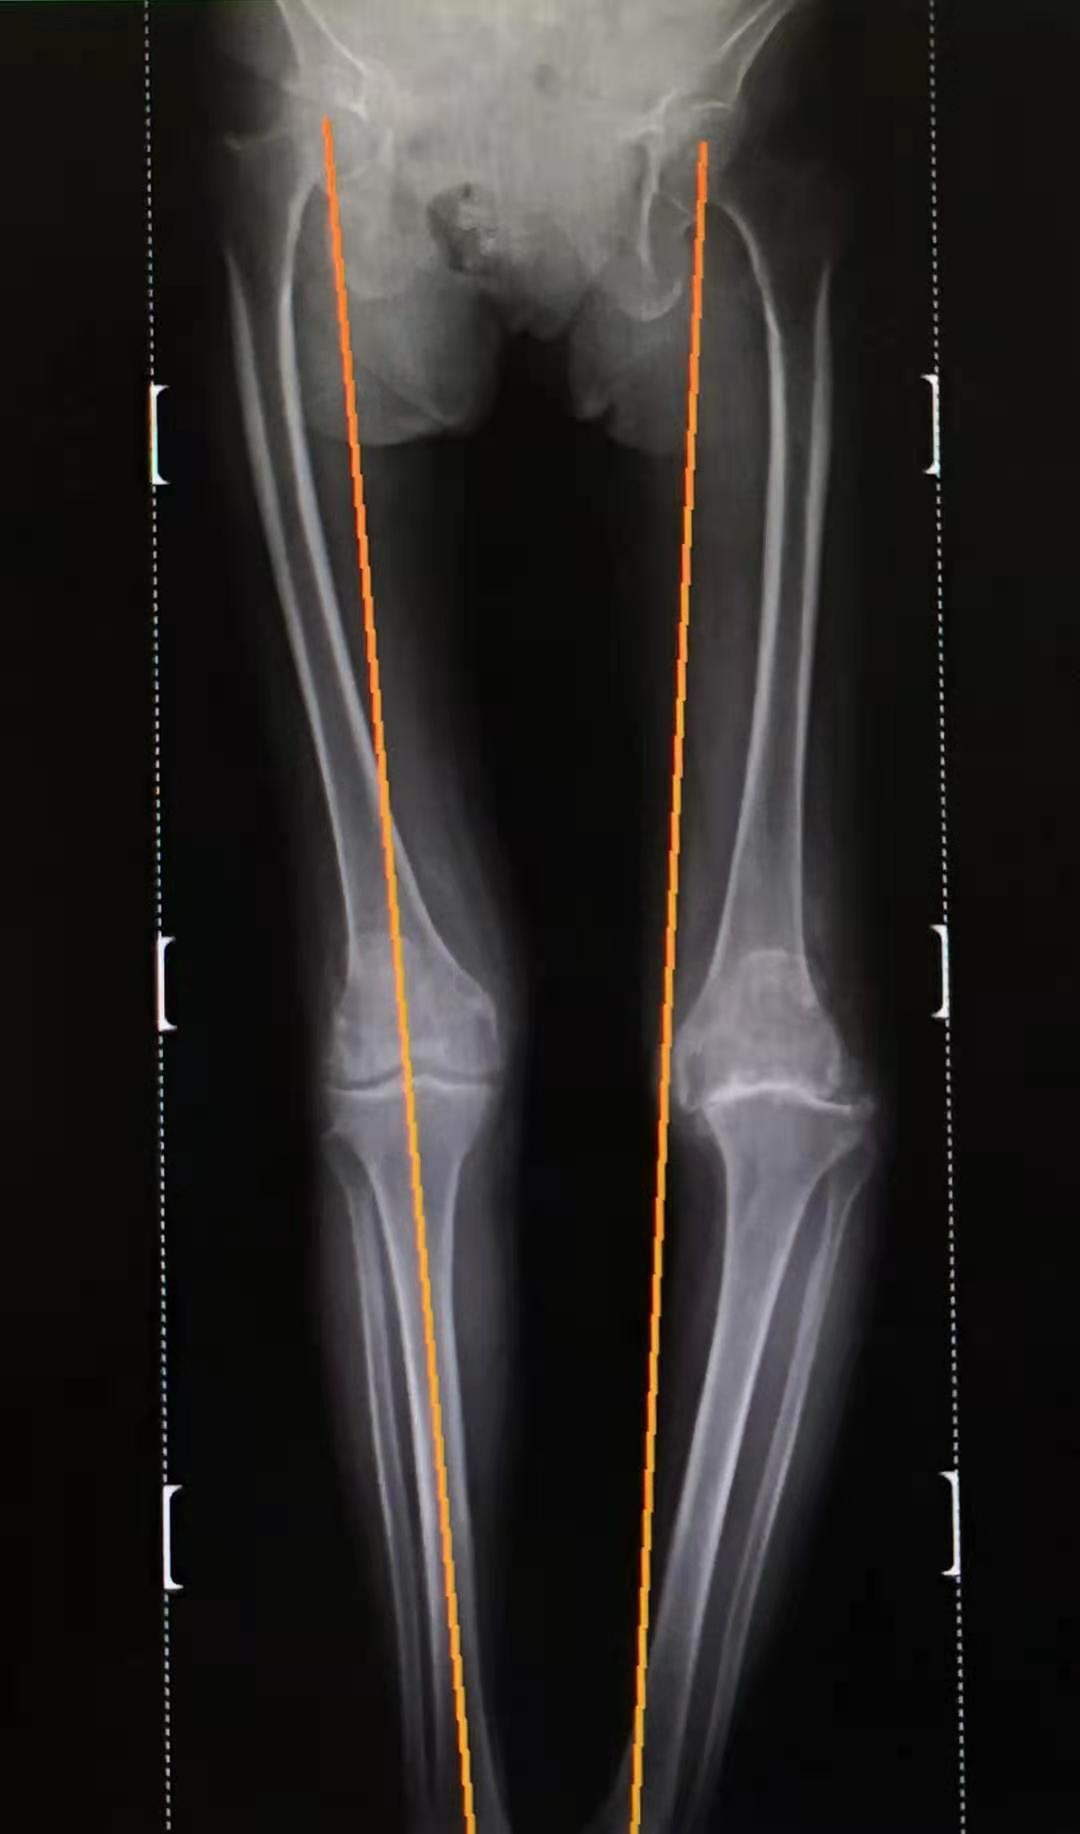

X线片显示双膝明显退变,以左膝较严重,关节间隙消失,关节面破坏,膝关节内翻畸形

双下肢负重力线显示左膝关节内翻程度